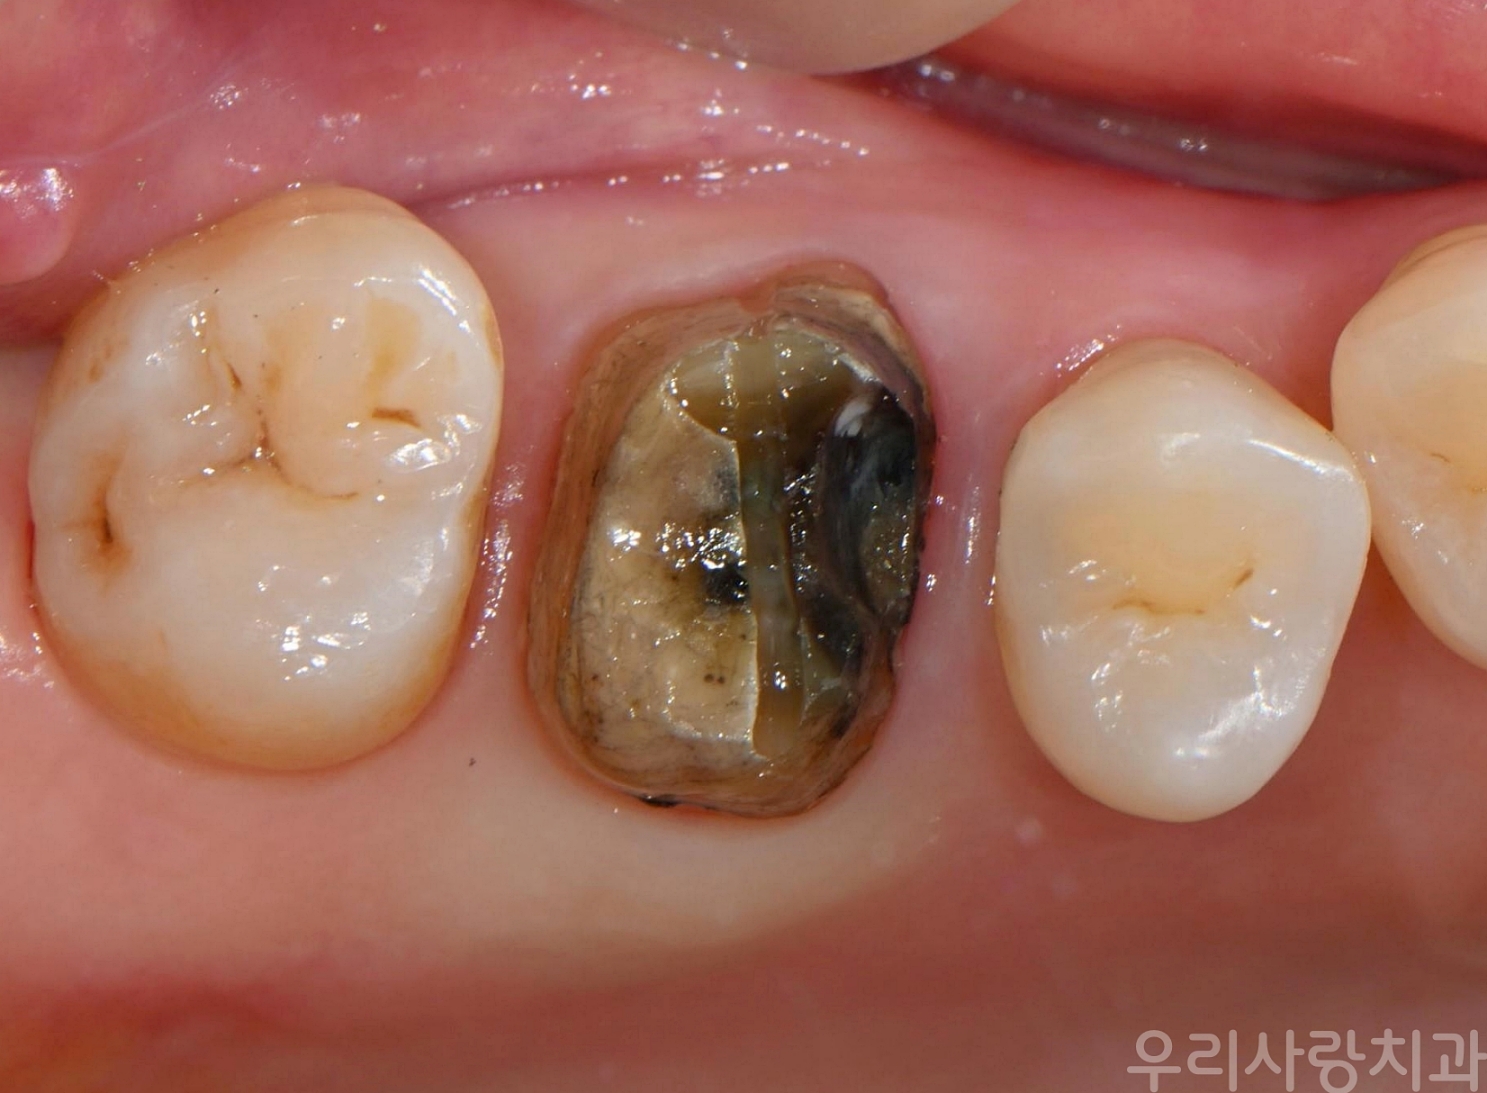

▲ 금니 제거 직후: 접착제는 녹아 사라졌고, 내부가 심하게 썩어있는 2차 충치 상태

예상대로 접착제(Dental Cement)는 이미 다 녹아 없어진 상태였고, 그 틈으로 오염물질이 들어가 치아 내부가 새까맣게 썩어 있었습니다. 이것이 바로 '2차 충치'입니다. 환자분은 전혀 통증을 느끼지 못하셨는데, 그 이유는 충치가 치아 내부의 신경까지 도달하지 않았기 때문입니다.

치아 신경은 깊숙한 곳에 위치합니다. 통증이 느껴질 때쯤이면 이미 충치가 신경까지 침범하여 신경치료가 불가피하거나, 심한 경우 발치를 해야 할 수도 있습니다. "안 아프다"는 것이 "건강하다"는 뜻은 아닙니다.